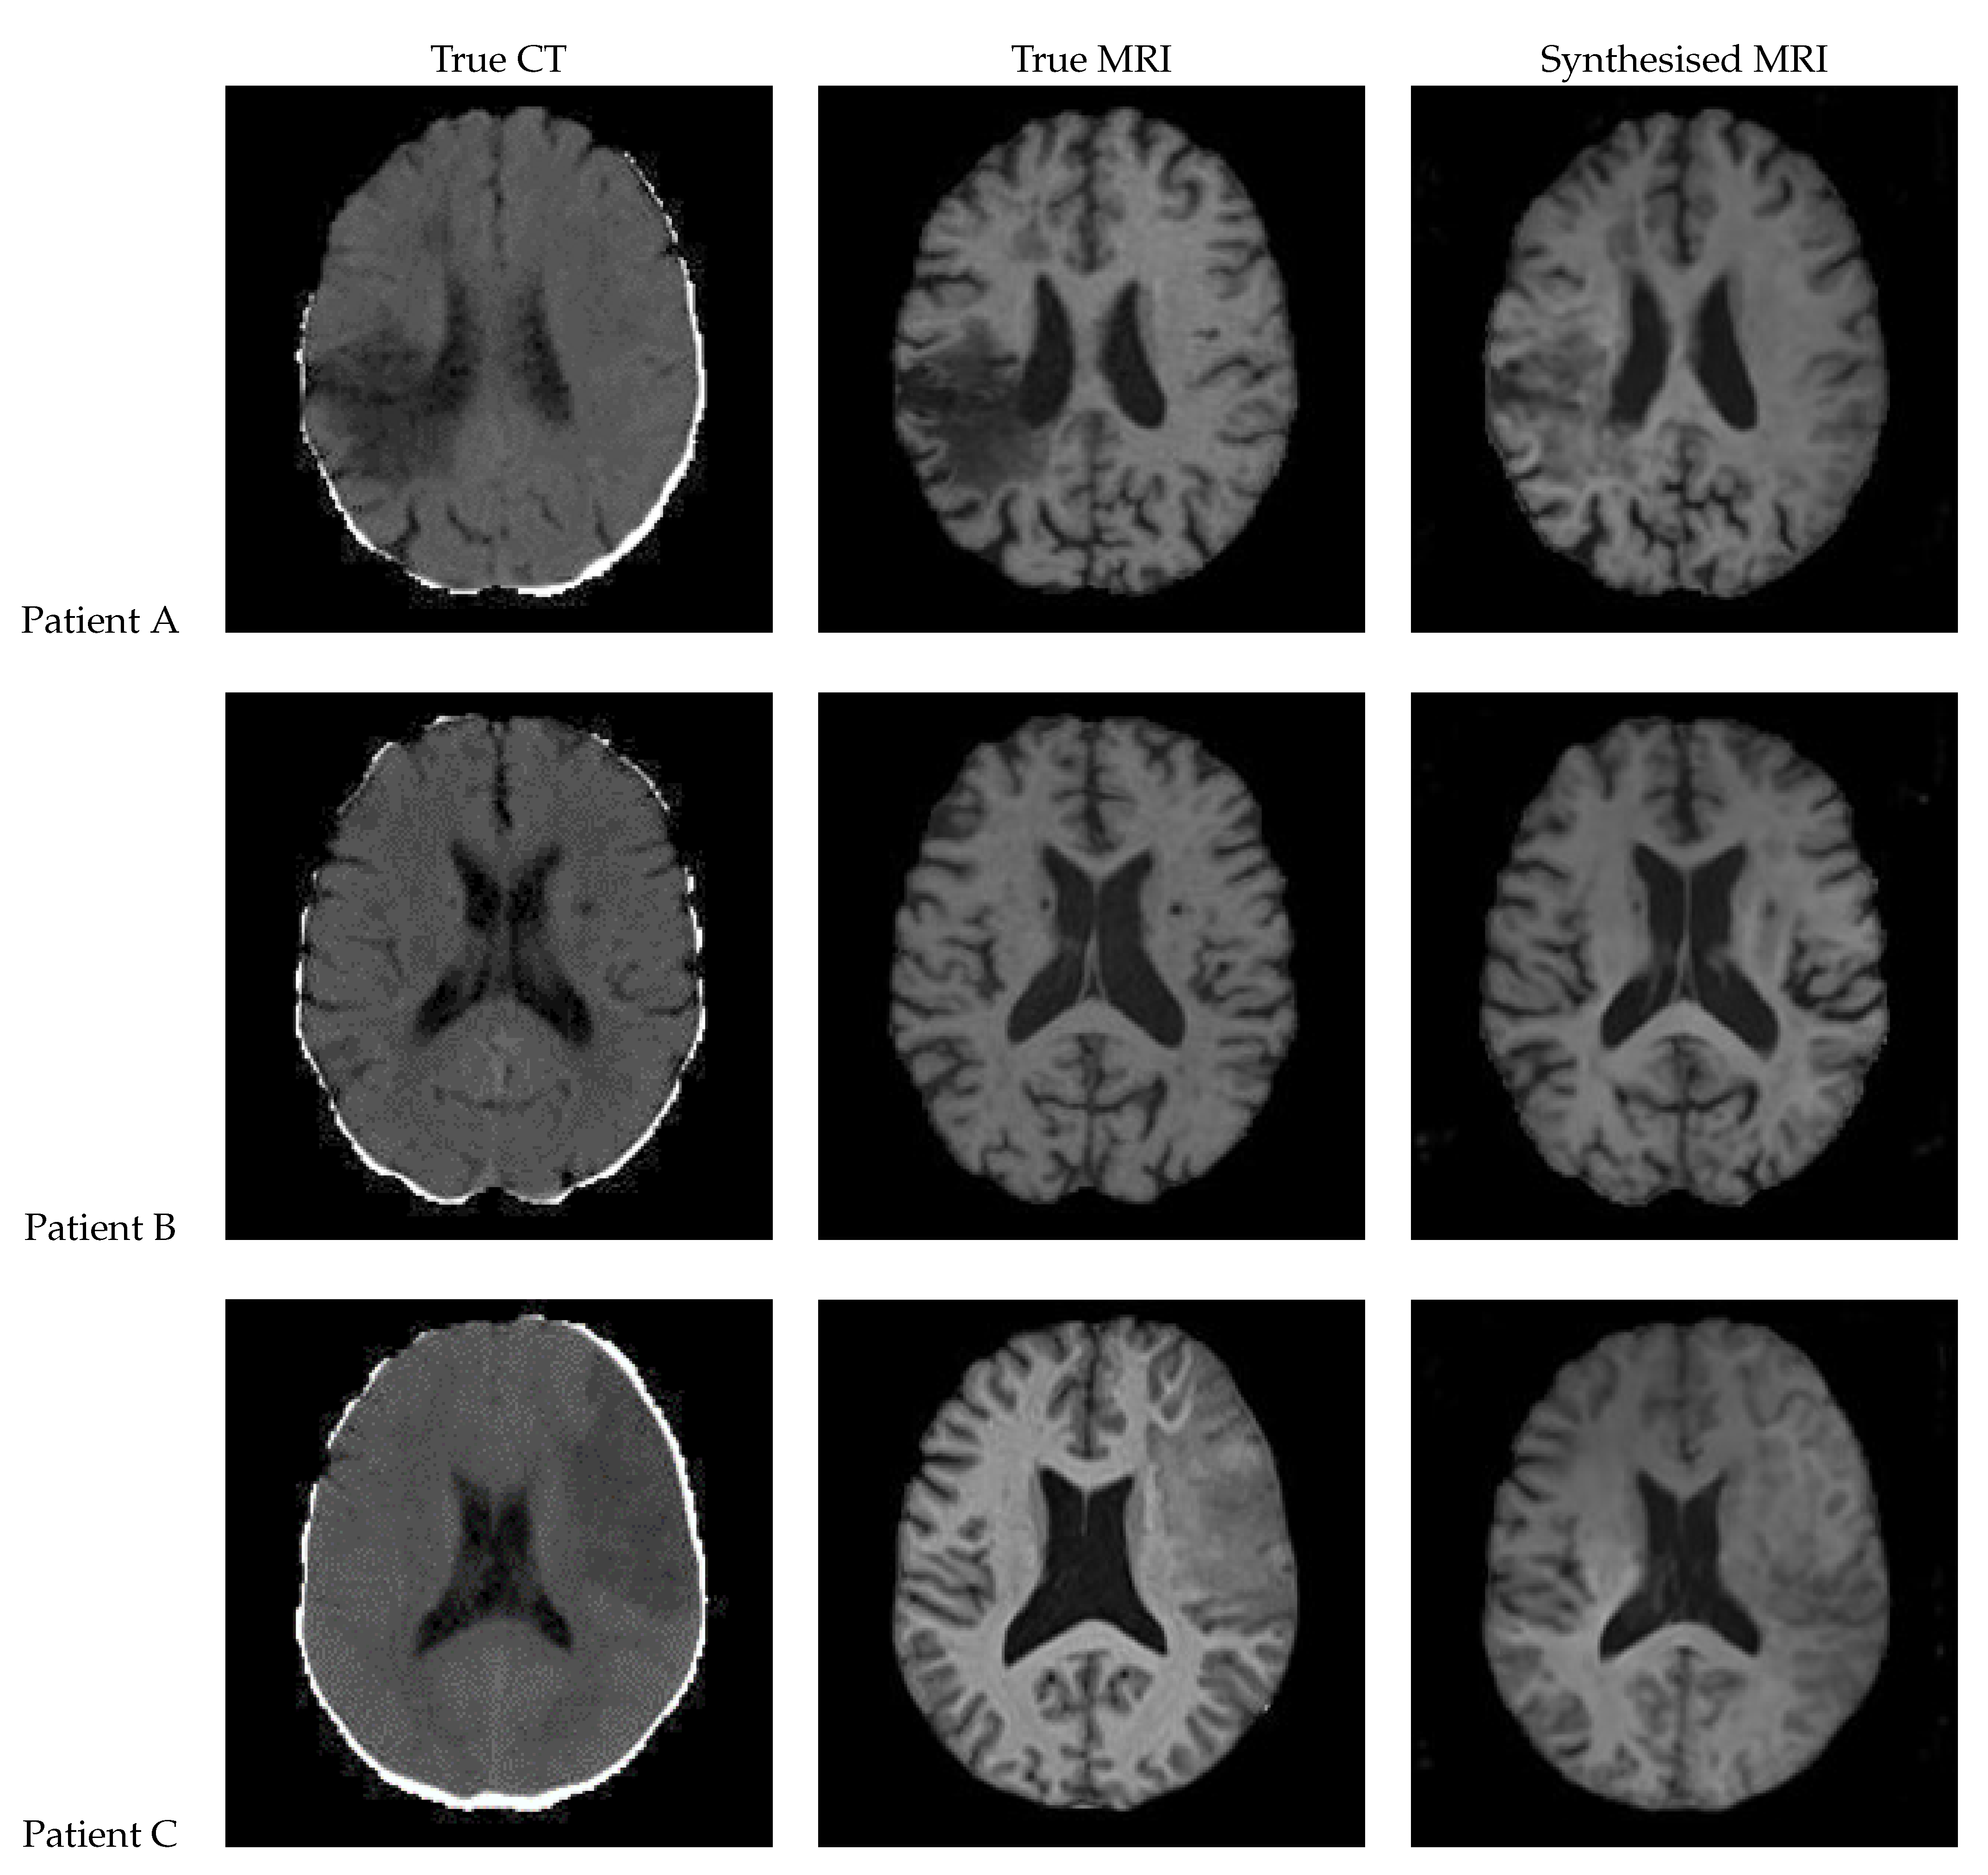

Figure 12 shows a sample slice of the synthetic MRI generated by a 3D UNet for three patients in the test set, along with the corresponding true MRI and CT slices. Patient A presents a large lesion, which can also be seen in the synthesised MRI, but with reduced contrast and less precise borders. Patient B shows a similar overall contrast to the true MRI. Patient C displays a very large, faint lesion that is not clearly visible in the synthetic MRI.

Figure 12. Axial slices of CT Scans (Left), True MRIs (Centre), and Synthetic MRIs generated by UNet (Right).

True CT True MRI Synthesised MRI

Patient A

Patient B

Patient C